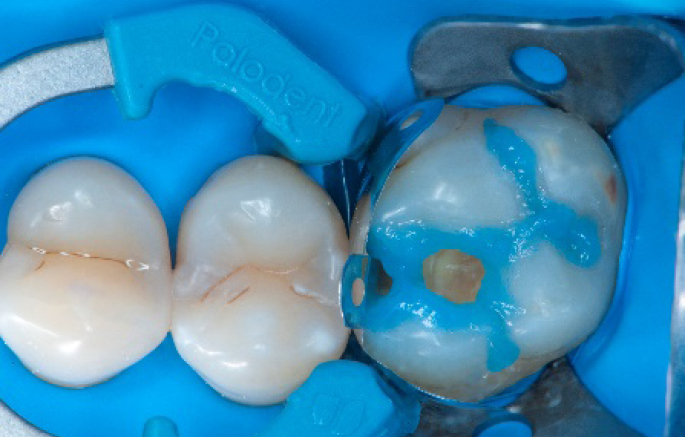

Step 6:

Selective enamel etching procedure with Conditioner2.

Step 7:

Adhesive application with a universal adhesive, Prime&Bond3.

Step 8:

Transformation of class II into class I, restoring the interproximal wall with Spectra ST4 composite in shade A2.

Step 9:

Transformation of a big class I into a small class I, using SDR® flow+ material in one increment up to 4 mm.

Step 10:

The situation after the application of SDR® flow+ material.